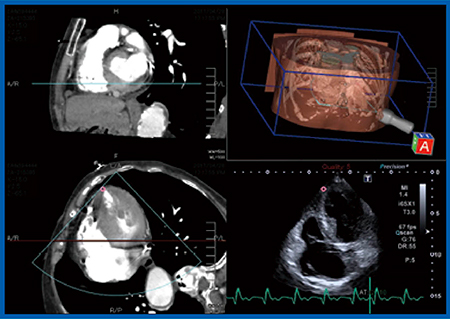

TAVIの実施に当たり,当院では心臓外科医が穿刺する直前に術中エコーにてリアルタイムに心尖部の位置を確認する。しかしながら,本症例は,呼吸機能障害により左肺が過膨張となっており,心尖部が肺の後ろに隠れてしまうため,体位変換が困難な術中には心尖部の描出ができなかった。そこで,Fusion Imagingにて術前のCT画像とリアルタイムの超音波画像を同一画面上に並べて同期表示したところ(図2),心臓外科医も納得し,自信を持って穿刺を行うことができた。

図2 症例:Fusion Imagingによる術前CT画像と術中超音波画像の同期表示